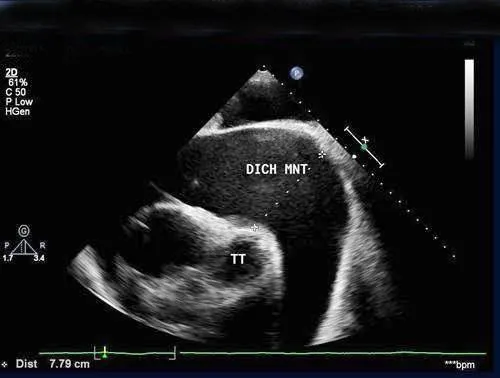

• Tràn dịch màng ngoài tim: * Siêu âm 2D: Phát hiện dịch tích tụ trong khoang màng ngoài tim, đánh giá số lượng và vị trí của dịch.* Phình tim và Giả phình: * Phình tim: Vùng thành tim bị giãn ra và mỏng đi. * Giả phình: Một vết rách trên thành tim được bao bọc bởi cục máu đông và màng ngoài tim. * Siêu âm 2D và Doppler: Xác định vị trí, kích thước, và đặc điểm của phình tim và giả phình.* Huyết khối trong buồng tim: * Siêu âm 2D: Phát hiện các khối máu đông trong buồng tim.* Thủng vách liên thất: * Siêu âm 2D: Có thể thấy lỗ thông trên vách liên thất. * Siêu âm Doppler màu: Phát hiện dòng máu chảy qua lỗ thông.* Hở van hai lá: * Siêu âm Doppler màu: Đánh giá mức độ hở van hai lá. * Siêu âm Doppler liên tục: Đo vận tốc dòng máu hở van.